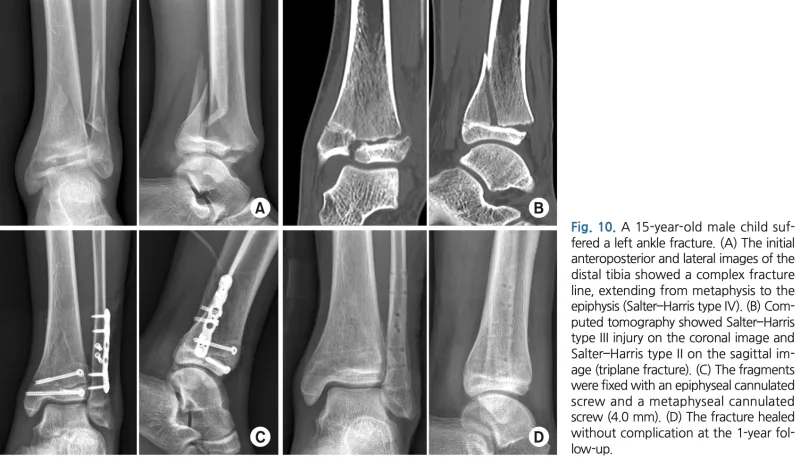

13時半から, 下腿骨遠位部骨折の高校生の手術.

腓骨は, 成長軟骨をまたがないように整復後にプレートとスクリューで固定.

脛骨遠位は, 整復後にスクリュー2本だけで固定しています.

引用元:Kim HY. Ankle fractures in children: Classification and treatment. J Musculoskelt Trauma. 2021. 34.

腓骨は, 遠位骨幹部で大きく転位しており, 整復した後にプレートで固定.

骨端線が残っている年齢のため, 骨端線を損傷しないよう, 骨端線より頭側のみにスクリューを入れる工夫が必要でした.